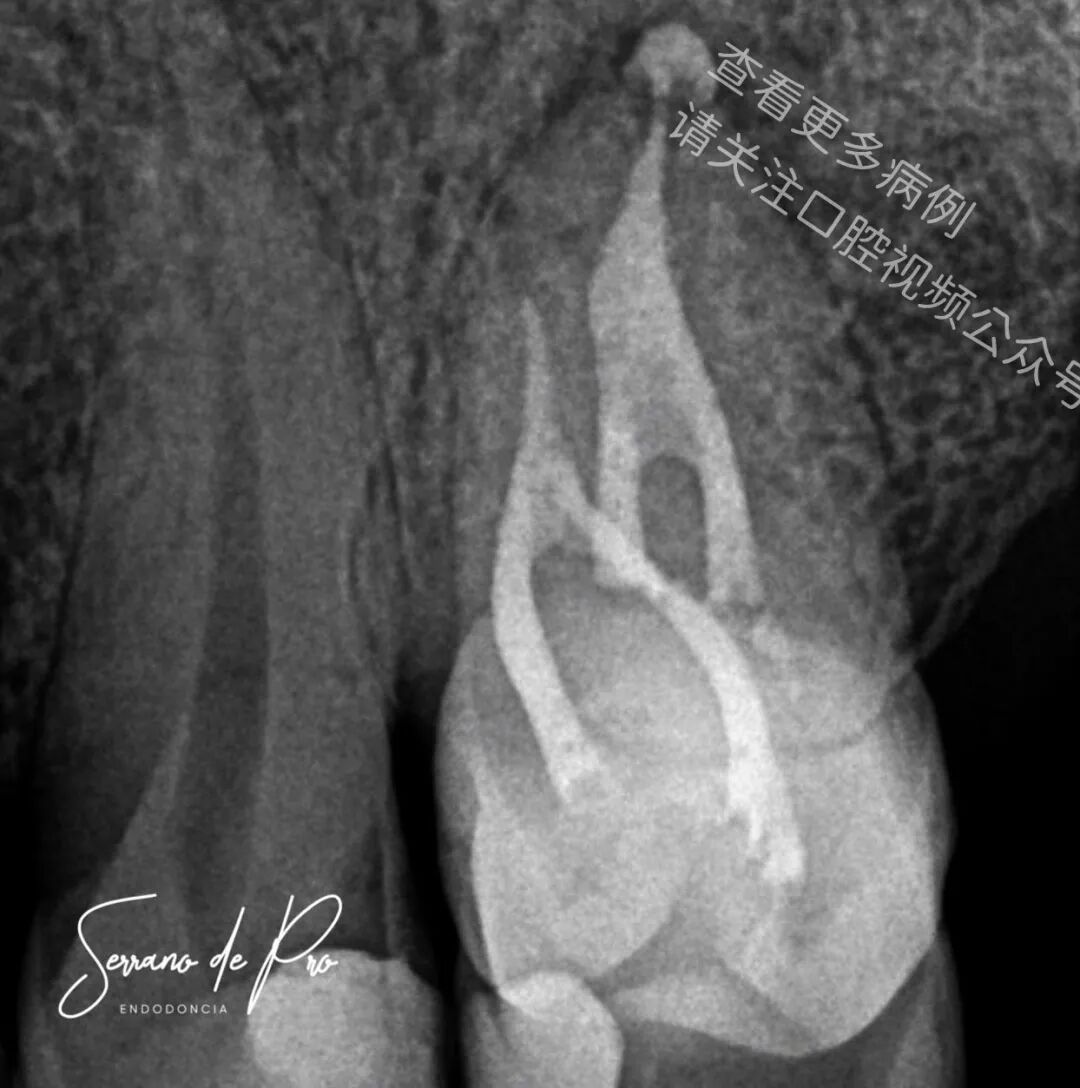

这是一个非常奇特的病例,24号牙和25号牙并非处于它们的正常位置,而是并排生长,拍出的X光片十分惊人。能如此清晰地看到根管充填的细节可不是每天都有的事。25号牙牙髓坏死,24号牙则患有严重的牙髓炎。

两颗牙都使用了来自FKG Iberia公司的Raceevo锉预备到30.04的锥度,并用Avalon Biomed公司的Neosealer Flo封闭剂以及Zarc4endo公司的产品配合WaveOne垂直加压(WVC)技术进行根管充填。

由于患者的病史,25号牙因存在禁忌证而未被拔除。